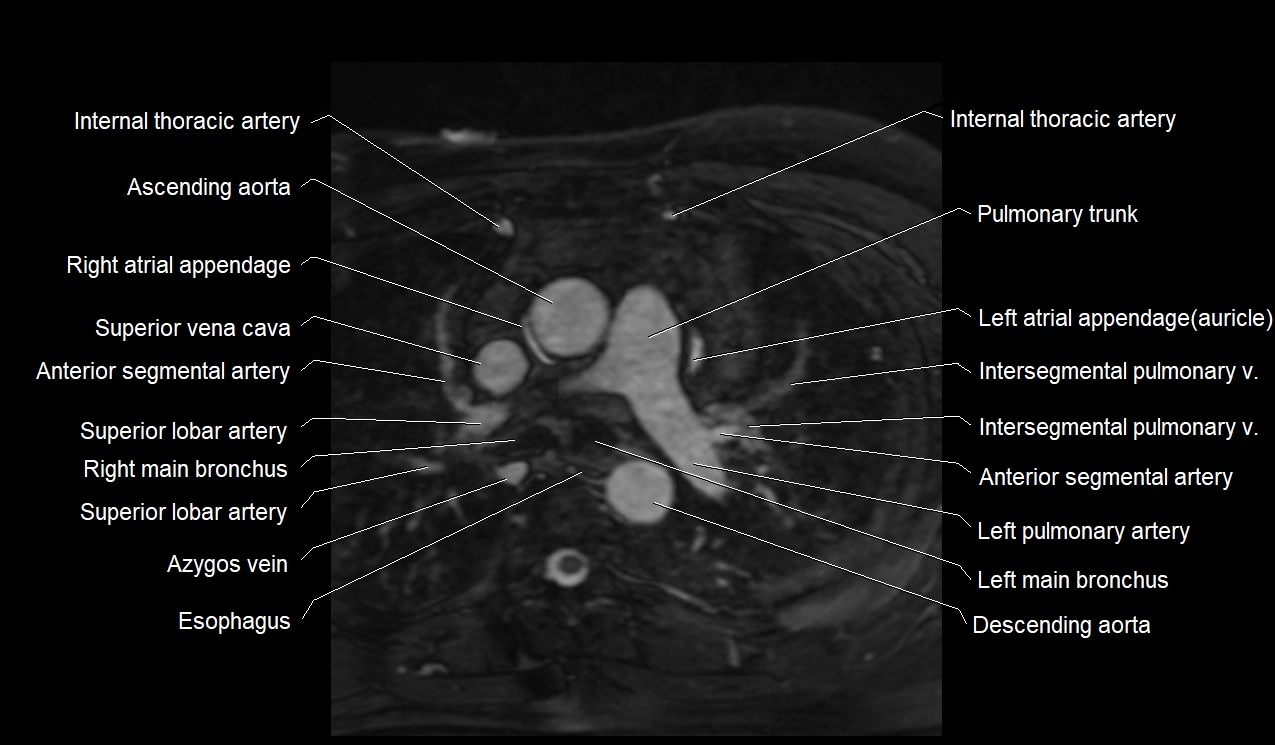

MRI image